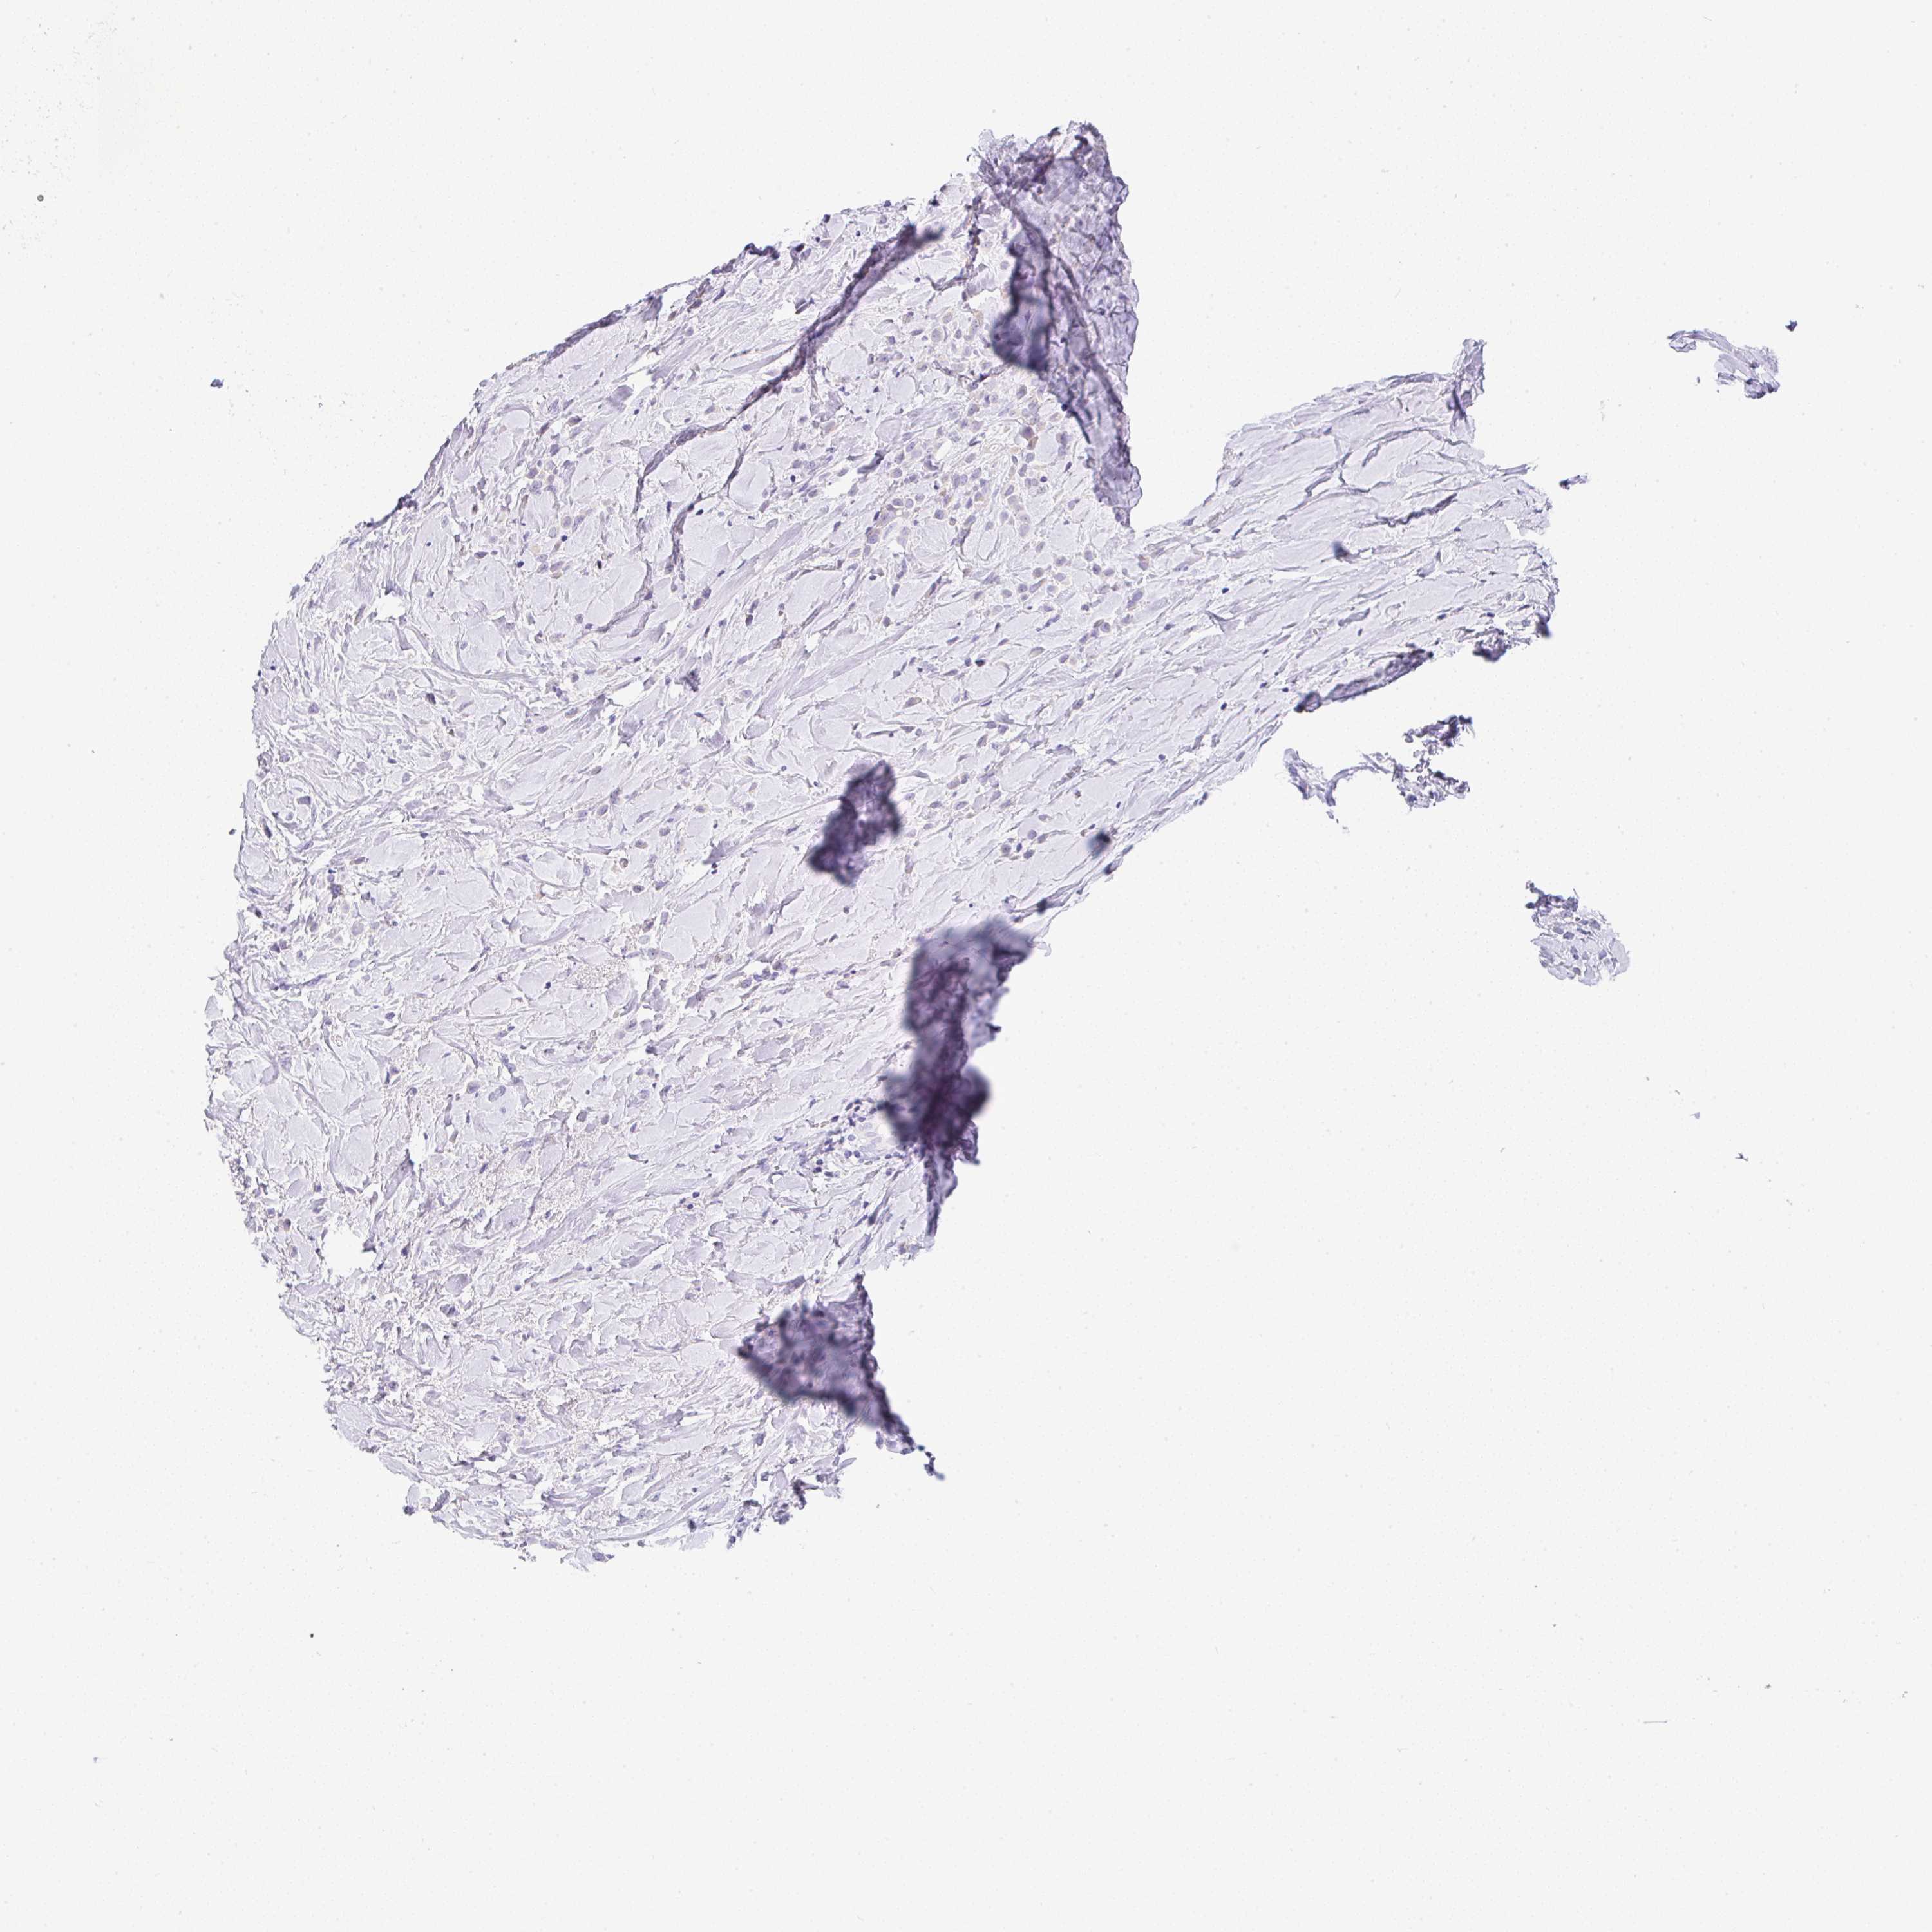

BRCA TCGA BRCA VALIDATION PROTEIN EXPRESSION

ANTIBODIES

AND

VALIDATION